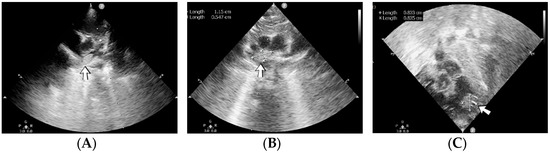

4.39. Case No. 39—Postnatal Thrombosis of Both Internal Jugular Veins, Both Brachiocephalic Veins, the Superior Vena Cava, the Inferior Vena Cava, Both Common Iliac Veins, Both External Iliac Veins, and Both Femoral Veins

A 6-week-old male neonate (29 weeks, 1.23 kg), the first twin from a twin pregnancy, known with cardiopulmonary arrest with prolonged cardiopulmonary resuscitation, presented with severe bronchopulmonary dysplasia. The admission laboratory findings showed leukocytosis, modified coagulation tests, elevated D-dimer tests, and sepsis with Pseudomonas aeruginosa. During hospitalization, the patient suffered multiple fractures of the humerus, femur, tibia, and costal ribs.

A cardiovascular ultrasound revealed thrombosis of the right internal jugular and brachiocephalic veins. Therefore, the central venous catheter from the right internal jugular vein was removed, and two other central lines were inserted on the right femoral vein and on the left internal jugular vein. Despite initiating anticoagulant treatment with heparin, followed by bivalirudin and fibrinolytic agents like alteplase, the CT angiography indicated an extension of the thrombus to the right atrium (Figure 18). A thrombectomy and pericardial patch venoplasty were performed at four months of age. Despite the double anticoagulation treatment with heparin and bivalirudin, the superior vena cava syndrome clinically persisted, and thrombosis of the left internal jugular and brachiocephalic veins also occurred. Thrombosis of the inferior vena cava, both common iliac veins, external iliac veins, and femoral veins were diagnosed in turn. The patient died at 14 months of life due to cardiopulmonary arrest.

Figure 18.

Case no. 39. During surgery, a fibrous band (A) was noticed between the right internal jugular and brachiocephalic veins. Thrombosis of the right internal jugular vein (B) and the superior vena cava (C) was identified on Angio-CT.

A suspicion of inherited thrombophilia was raised, and genetic testing confirmed it, with a positive MTHFR C677T homozygous gene mutation and antithrombin deficiency. Normal PAI-1 levels were detected. There was a positive family history of thrombosis—the second twin from the delivery, who died at six weeks of life, presented cerebral venous sinus thrombosis on the brain ultrasound from admission.